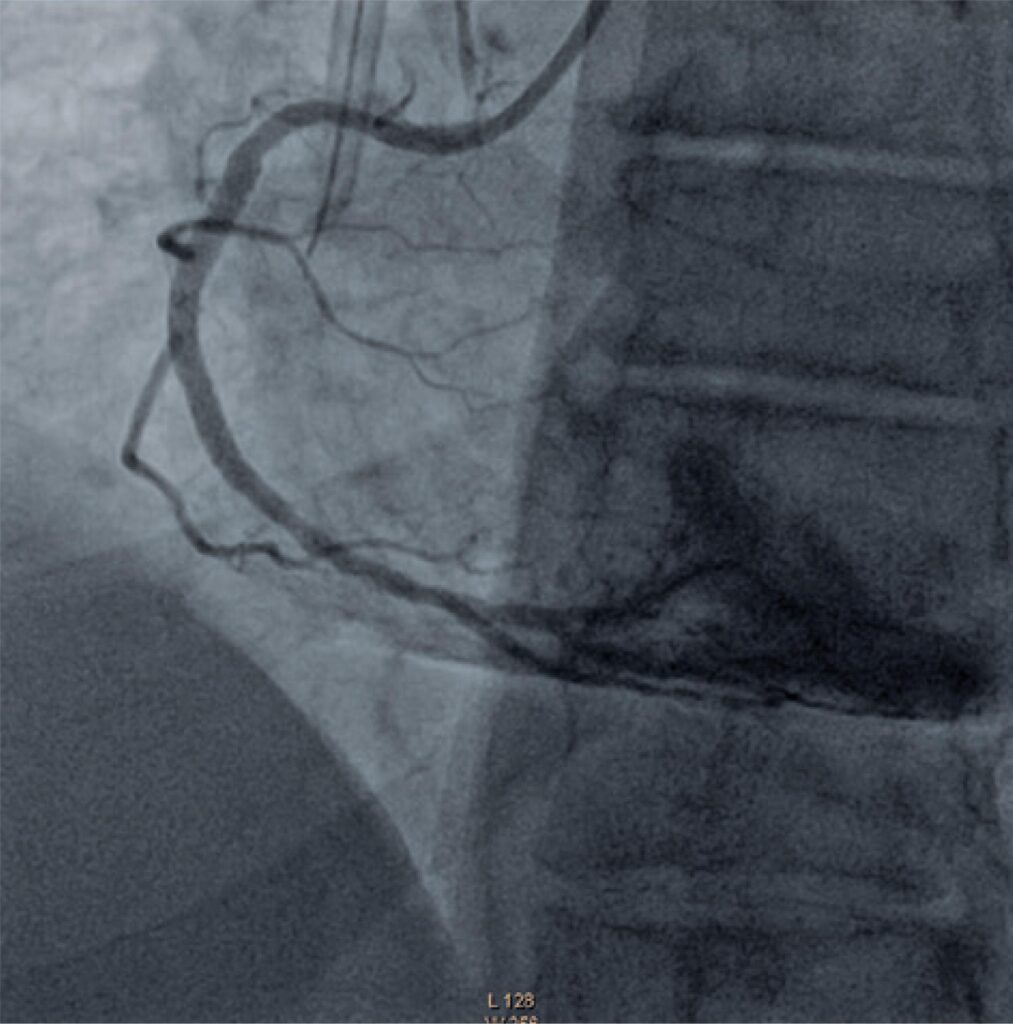

Figure 4

Angiographic control after stent implantation in the right coronary artery.